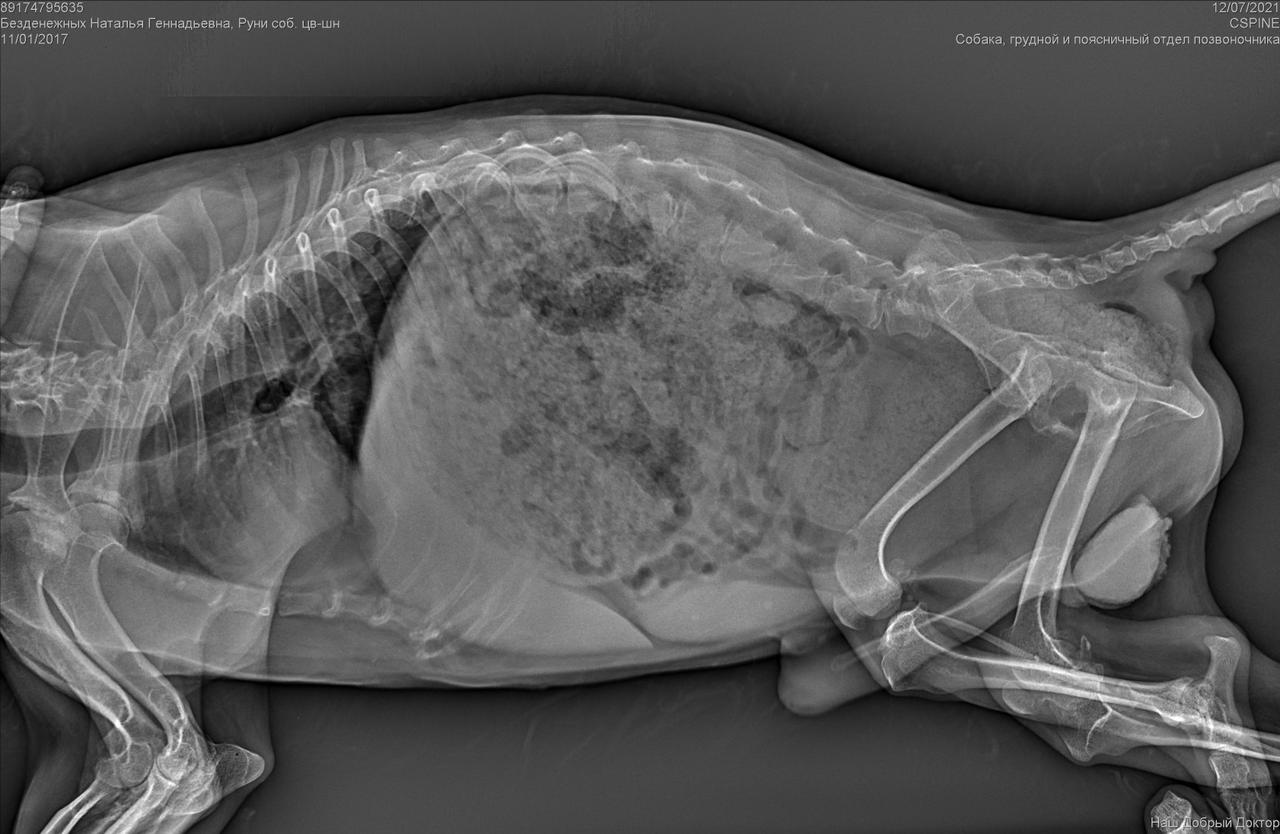

С собакой сегодня поедут в клинику. Передержать и полечить смогут. Попросила в клинике посмотреть клеймо и посканировать ип.

ПОнадобится наша помощь с оплатой лечения и поиском дома.